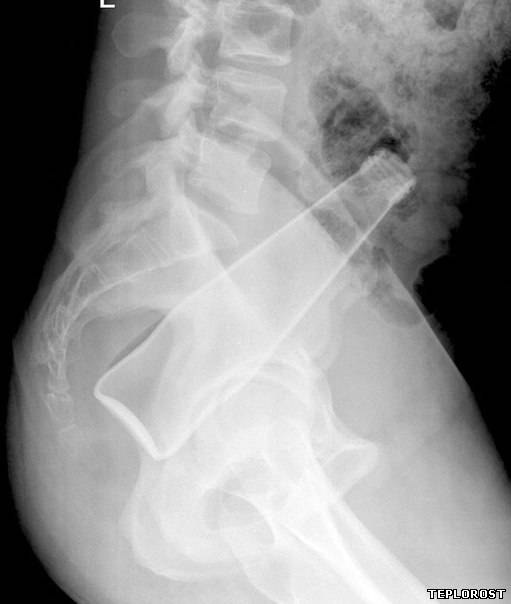

Забытые во время операции хирургические ножницы